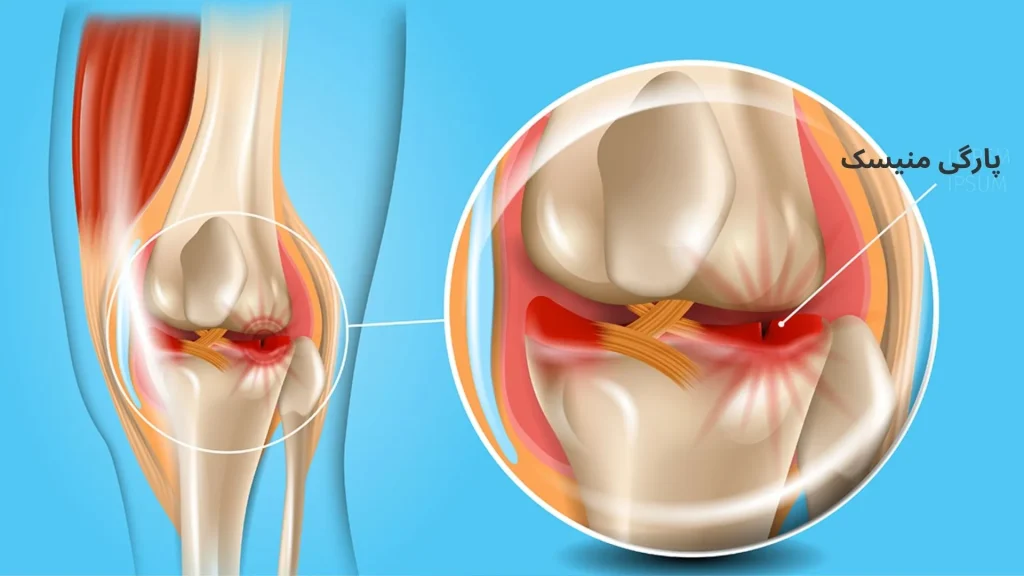

زانو یکی از مفاصل اصلی بدن است که فشار زیادی را در طول روز تحمل میکند. درون این مفصل، دو ساختار حیاتی به نام منیسک زانو قرار دارد که مانند ضربهگیر عمل کرده و از تماس مستقیم استخوانهای ران و ساق پا جلوگیری میکنند.

وقتی منیسک زانو آسیب ببیند یا پاره شود، درد، ورم، صداهای غیرعادی و محدودیت حرکتی در زانو ایجاد میشود.

منیسک زانو چیست و چه نقشی دارد؟

در هر زانو دو عدد منیسک وجود دارد:

منیسک داخلی (Medial Meniscus)

منیسک خارجی (Lateral Meniscus)

هر کدام از این منیسکها تکهای از غضروف نیمماهشکل و فیبری هستند که بین استخوان ران (Femur) و استخوان ساق پا (Tibia) قرار گرفتهاند.

اگر منیسک آسیب ببیند، مفصل زانو ثبات خود را از دست میدهد و فشار غیرطبیعی به سایر ساختارها مانند رباطها و غضروفها وارد میشود.